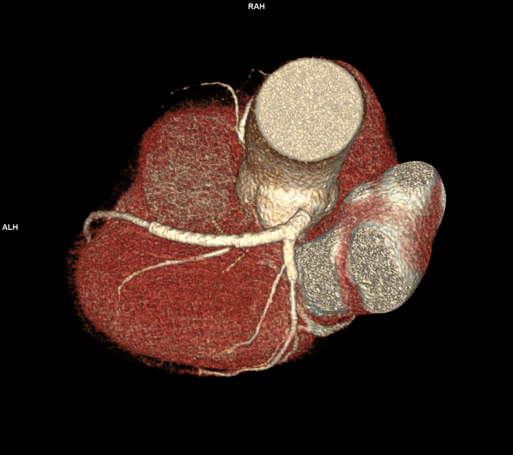

Stenturile situate proximal la nivelul arterelor coronare au lumen suficient de mare ca să poate fi vizualizat prin CT, însă cu cat lumenul e mai mic şi / sau cantitatea de metal din peretele stentului este mai mare, lumenul stentului e mai greu de vizualizat. Examinarea CT NU poate vizualiza sensul de curgere al sângelui, de aceea faptul că după stent se pune în evidenţă densitate intraluminală egală cu cea din vasele de vecinătate, nu înseamnă ca stentul este permeabil; contrastul poate că a ajuns aici prin colaterale ca flux retrograd.

Stenturile coronariene proximale sunt în general corect evaluate prin examinare angioCT cardiacă cu sincronizare ECG pe aparate cu cel putin 64 de detectori. Prin examinare CT nu se poate vizualiza sensul de curgere a sângelui.